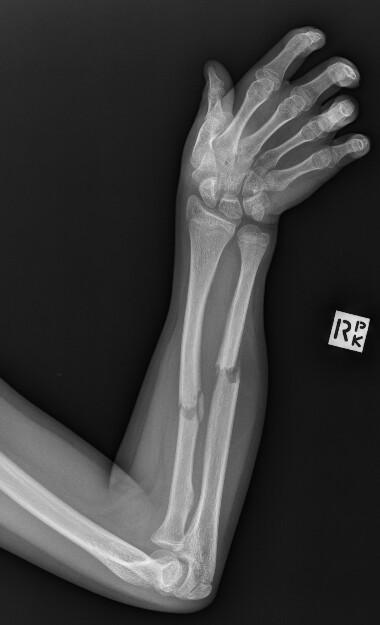

Maciej Debowski, Radiopaedia.org. From the case rID: 66146

Bascule postérieure (= fracture de Pouteau-Colles) : avis chirurgical. Réduction en flexion ulnaire et flexion palmaire et immobilisation par attelle plâtrée postérieure.

Bascule antérieure (= fracture de Goyrand-Smith) : avis chirurgical. Immobilisation par attelle plâtrée postérieure en position neutre.